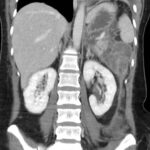

Caso 3

Mujer de 36 años que ingresa a Hospital Sanatorio Franchin el 11 de octubre de 2023 de forma programada para realización de duodeno pancreatectomía cefálica por tumor de cabeza de páncreas en estudio. Refiere hallazgo de lesión en forma incidental durante estudio de control hace dos meses por presentar antecedentes familiares (neoplasia endocrina múltiple). Se interna para manejo quirúrgico. Estudios de tomografía revelan formación nodular localizada en cabeza y cuerpo pancreático de paredes gruesas que mide 24 x 28 mm, que en resonancia se muestra hiperintensa en T2 y realce periférico luego de la administración de contraste endovenoso. Presenta restricción en la difusión con caída de la señal ADC, por lo que se vincula con una lesión de alta celularidad.

Laboratorios clínicos: Hto: 42 HB: 14.1 GB: 4200 Plaq: 231mil Glu: 90 Péptido C: 3.5 TGO: 17 TGP: 28 BT: 0.75 Fal: 179 Glucemia 109 TP: 100% KPTT: 36 Prots tots: 6.5 AlB 4.43.

Estudio histopatológico reveló neoplásica de estirpe neuroendocrina bien delimitada.